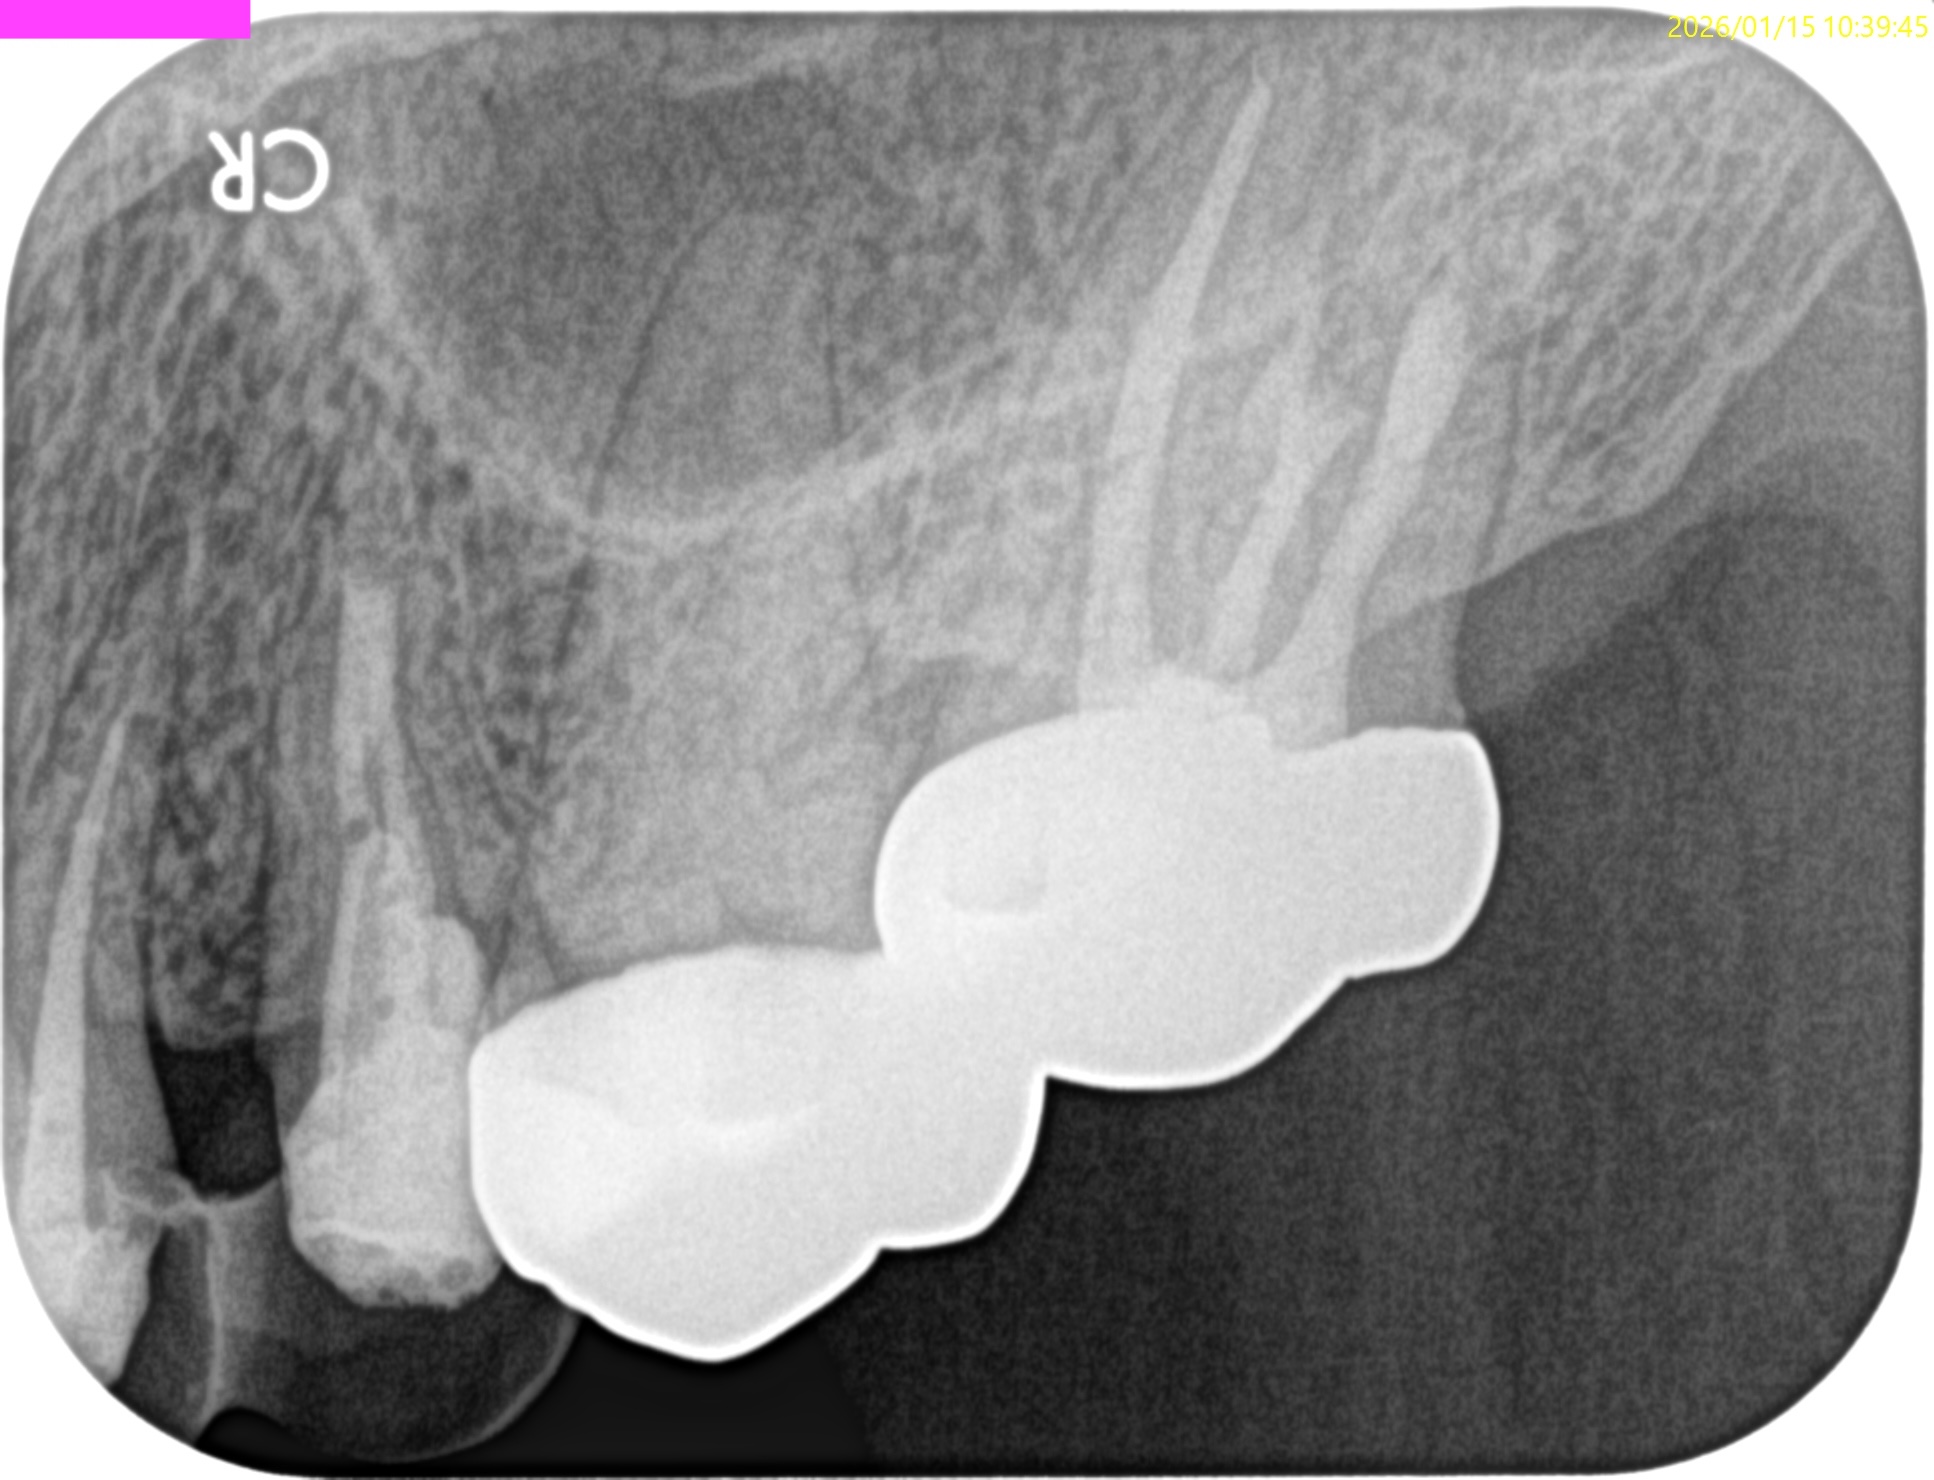

左上7番のMB,DBをApicoectomyしたと言う珍しい?ケースだ。

#15 MB,DB Apicoectomy 1yr recall(2026.1.15)

P

B

術前の根尖病変、術直後の歯槽骨の欠損は完治した。